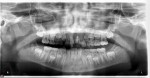

This is a 9yo girl with a high esthetic desire (wants to be a model/actor). She avulsed tooth #9 about 3 years ago, and she has been under treatment with other endodontists. I guess they attempted revascularization with MTA about year ago. #9 is ankylotic with a few mm’s infraposition. It is gray due to the MTA. #8 is slightly yellow/white due to calcification/obliteration but she says she feels cold testing and it is otherwise asymptomatic.

Gary for this patient a periodical film would help – the issue is NOT endo but the defect caused by eruption of the adjacent teeth – the PA film shows there is a vertical defect now that can be managed. The best thing would be to make sure there is a seal in the canal, then bleach the coronal part of the restoration, after which an additive type restoration to build out the rest of the clinical crown for esthetics – lithium disilicate would be my first choice of material to use.

Then someone has to watch for her growth spurt – and as soon as it happens the tooth has to be removed – this will reduce the defect that will become much more on the growth of the maxilla – there is also some discussion about whether the ankylosed tooth will affect maxillary growth – this is much like placing an implant too early but worse. Orthodontic care for this potential movie star should also be delayed because any treatment now would have to be worked around this tooth and any eruptive force would created a vertical periodontal defect that might jeopardize the adjacent teeth.